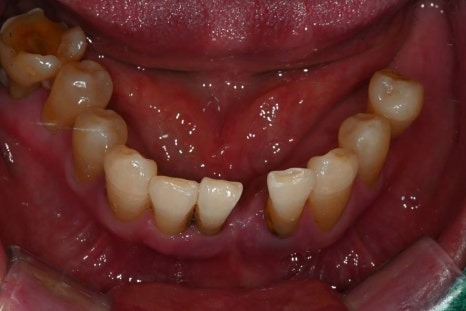

이번에 소개해드릴 환자분은

당뇨와 고혈압, 두 가지 전신질환을

모두 가지고 계셨던 분으로

치아 결손이 광범위해

전악 임플란트가 필요한 상황이었습니다.

· 상악은 잇몸뼈가 매우 얇고 치아가 거의 남아 있지 않은 상태

· 하악은 부분 결손과 앞니의 심한 동요

· 식사가 어려울 정도로 기능 저하가 심한 상태